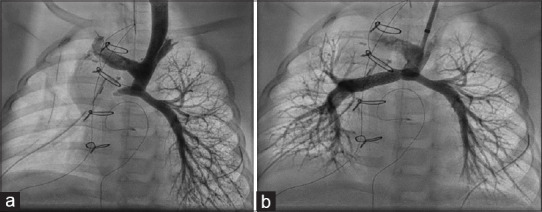

Background: Branch pulmonary artery (PA) stenosis must be addressed early to prevent right ventricular scarring and establish lung blood flow. Balloon-mounted stents are more useful in managing right ventricular outflow tract (RVOT) obstruction and PA stenosis.

Materials and methods: We studied the clinical and angiographic data of children with congenital heart disease who underwent stenting for RVOT obstruction and branch PA stenosis using the Formula stent (Cook Medical, Limerick, Ireland) between 2018 and 2024 in a tertiary pediatric cardiac center in southern India.

Results: Our patient cohort included 65 patients with a median age of 3 years (range: 3 months to 17 years). The median weight of patients was 11.5 kg (4.8-60.4 kg), with 40% weighing <10 kg. Out of the 87 stents implanted, four stents were implanted in RVOT, while the rest were branch PA stenting. The median stent length was 20 mm (12-60 mm), and the median stent diameter was 10 mm (5-10 mm). All stents were deployed using 5Fr to 8Fr sheaths or guiding catheters. The median procedure time was 62 min (20-170 min), with a median fluoroscopy time of 15 min (4-110 min). A total of 17 (19%) stents in 14 patients required further dilatation at a mean interval of 25 ± 4 months from the time of stenting. Ballooning resulted in an increase in diameter from 7.8 ± 2.2 mm to 10.2 ± 1.7 mm. Right ventricular systolic pressure had reduced from 70.3 ± 8 to 40.1 ± 1 mmHg after balloon dilatation in patients with a biventricular heart.

Conclusion: The Formula stent provides a comprehensive stent size option, requiring smaller sheaths, reduced procedural time, minimum complications, and an acceptable rate of reinterventions.